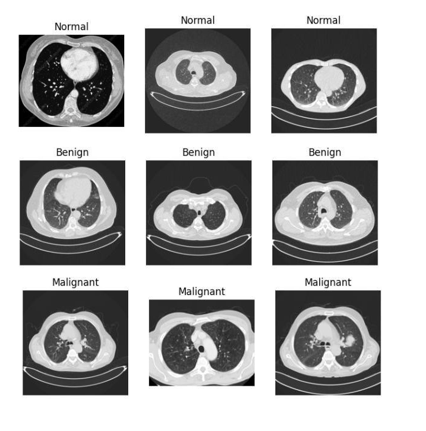

Comparative Analysis of Machine Learning Models for Lung Cancer Detection Using CT Scan Images

Muhammad Osama, Ejaz Ahmed, Misbah Batool, Mohsin Saleem, Ahmed Salim

318-328